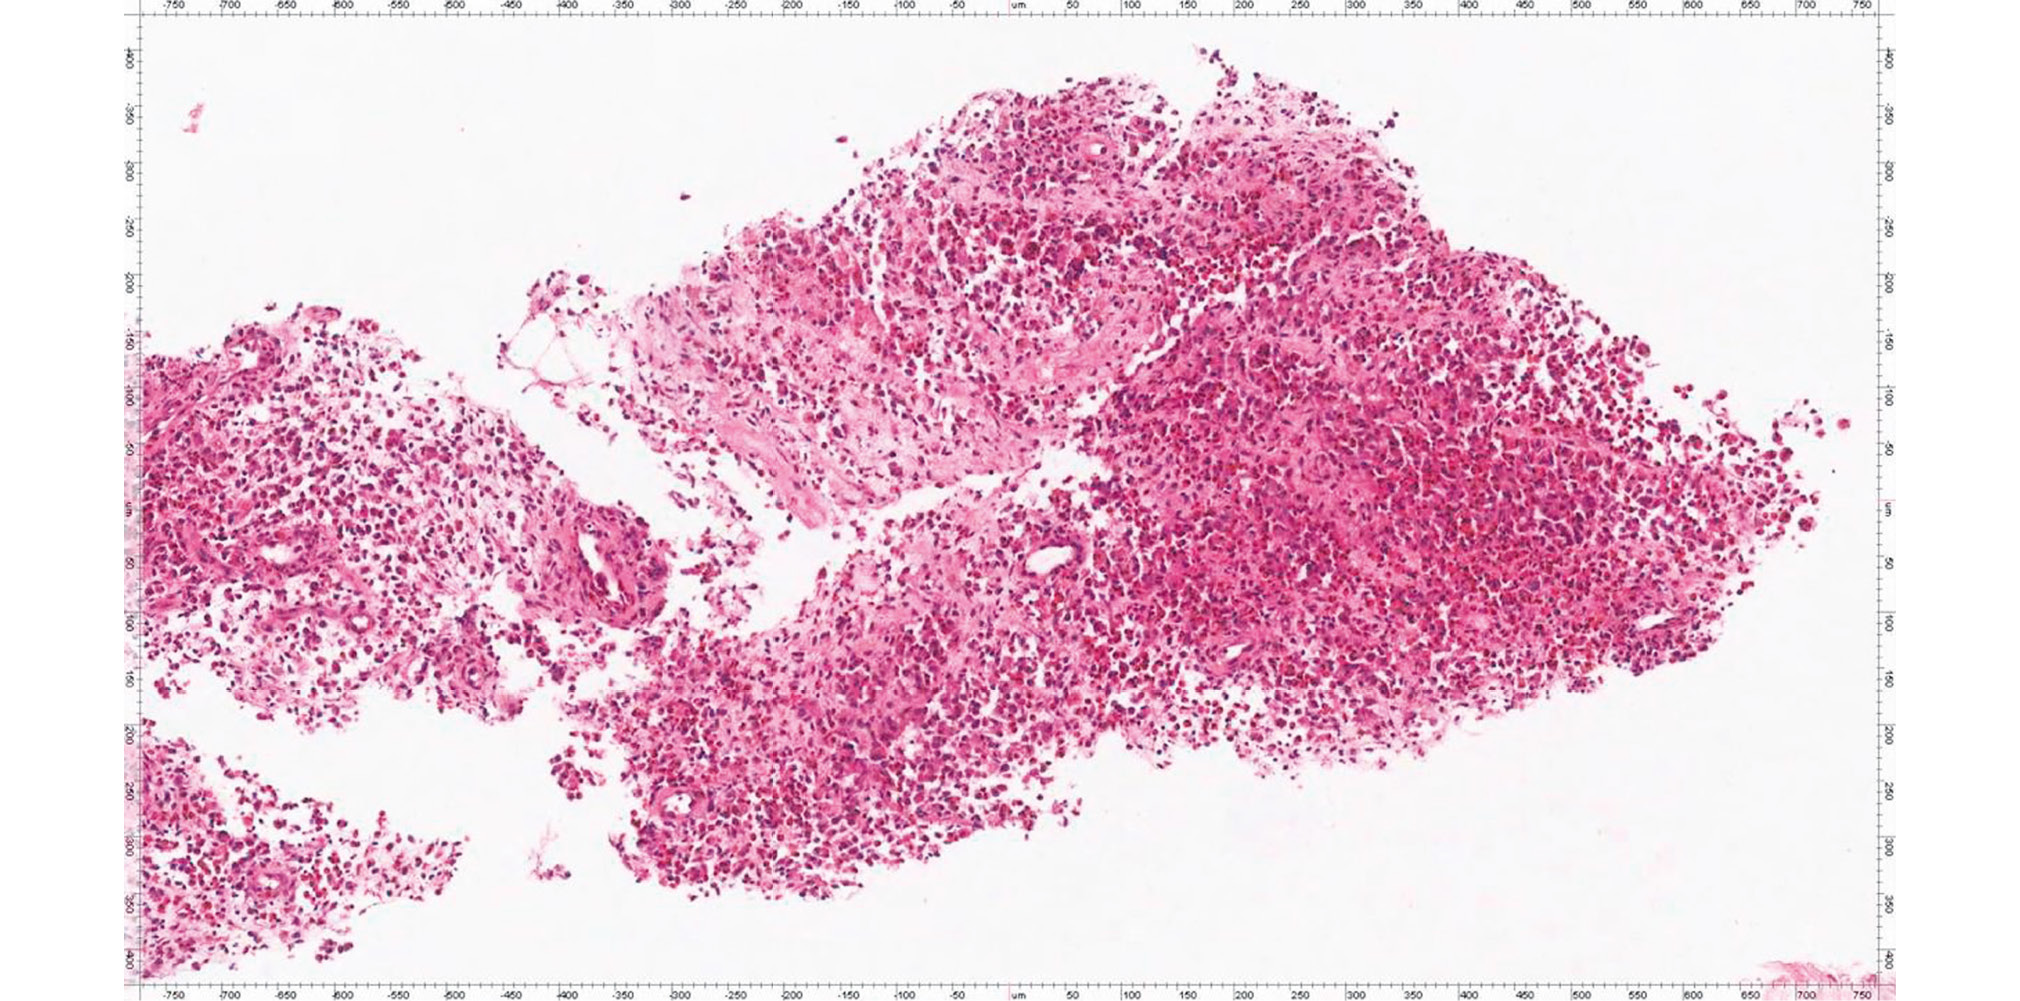

CT-guided 18G needle biopsy was performed from the wing formation of the left iliac bone (Fig. 3). The histological study (No. 2017-10802-01) concluded on the morphoimmunohistochemical presentation, which is most consistent with Langerhans cell histiocytosis (eosinophilic granuloma, histiocytosis X) (Fig. 4).

Fig. 4. Histological specimen: fibrovascular tissue fragments with polymorphic-cellular infiltration consisting numerous granulocytes, including an abundance of eosinophils, plasma cells, and individual cells with bean-shaped nuclei are noted. Hematoxylin-eosin staining ×200.

Solitary eosinophilic granuloma of bone is a relatively uncommon occurence, accounting for less than 1% of tumor-like bone lesions. A histological sign of histiocytosis X, including eosinophilic granuloma, is the presence of proliferating histiocytes (Langerhans histiocytes) [1]. The histiocyte contains puffed oval nuclei and eosinophilic cytoplasm. Bimbek granules are cytoplasmic organelles found in Langerhans cells, but their function is still unclear. The granuloma also comprises a large number of eosinophils and giant multinucleated cells.